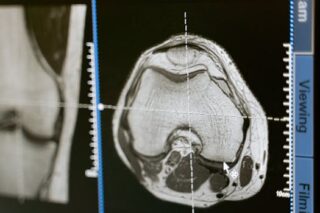

In addition to ultrasound, other imaging techniques such as MRI and CT scans can be used to provide more detailed, complementary images. These methods can emphasize tissues that are difficult to distinguish on standard ultrasound due to their isoechoic nature.